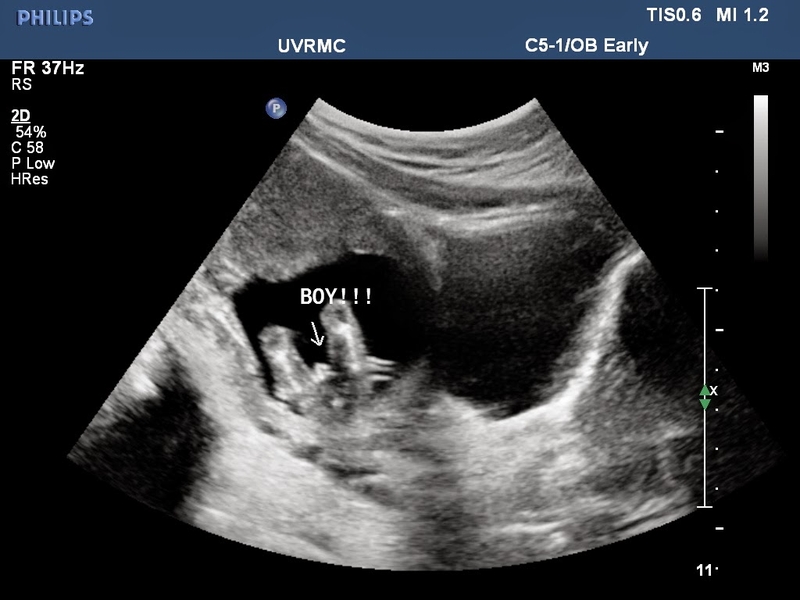

Đối với những thai phụ vẫn chưa biết mình bắt đầu mang thai từ bao giờ, bác sĩ sẽ khuyên mẹ làm siêu âm vào giai đoạn khoảng 18 - 23 tuần. Nếu đúng như dự kiến, cơ thể trẻ đã hình thành được những bộ phận quan trọng nên bác sĩ có thể quan sát được những bất thường mang tính phức tạp hơn như: